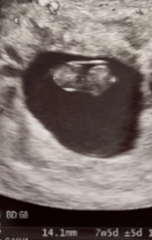

Been looking at my only ultrasound image of ‘nugget’ and realise I don’t actually know what I’m looking at.

Can anyone with knowledge of reading ultrasound images please help? Can you tell from this image which end is baby’s head? Not sure why it matters but for some reason it does.

@DevonEma Not an ultrasound expert but from the pictures I think on the left one your baby's head is the too part of the baby and the second picture shows the baby on his or her side with their head to the left. That's what I see but I could be wrong,